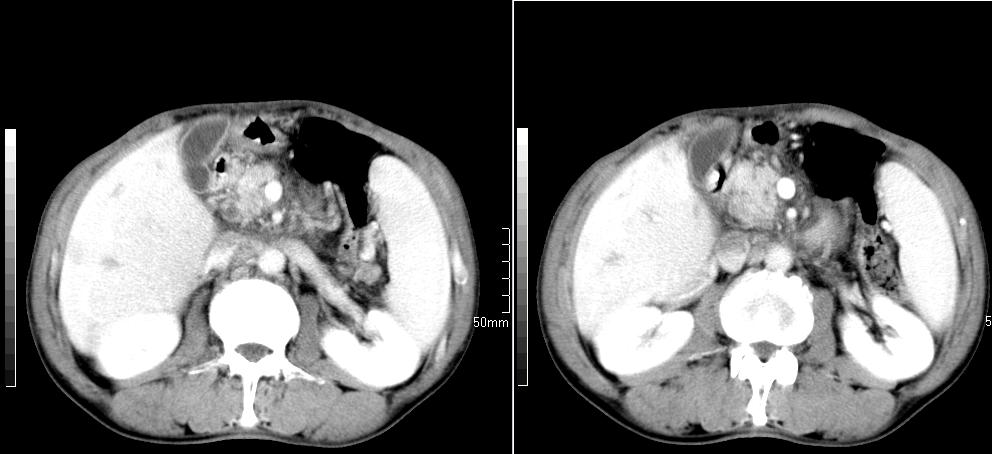

标题: CT26769:男,58岁,腹胀、腹部不适一年余 [打印本页]

标题: CT26769:男,58岁,腹胀、腹部不适一年余

肝右叶后段见小片状略低密度影,边缘不清,轻度强化,内见小血管影通过同,延迟期为等密度,考虑局灶性脂肪浸润。需与血管瘤鉴别。另有胆囊炎、脾大。

肠系膜脂膜炎,胆囊炎,脾大。建议结合临床。鉴别:慢性胰腺炎并假囊肿形成。

1 慢性胰腺炎并假囊肿形成。2 慢性胆囊炎并累及肝边缘!

1)考虑慢性胰腺炎并假性囊肿形成。2) 慢性胆囊炎。3)肝内胆管扩张。

1肝内胆管扩张,性质待定,2慢性胰腺炎胰管扩张,胰腺颈部假囊肿,3肝左叶低密度为小囊肿,4胆囊炎。